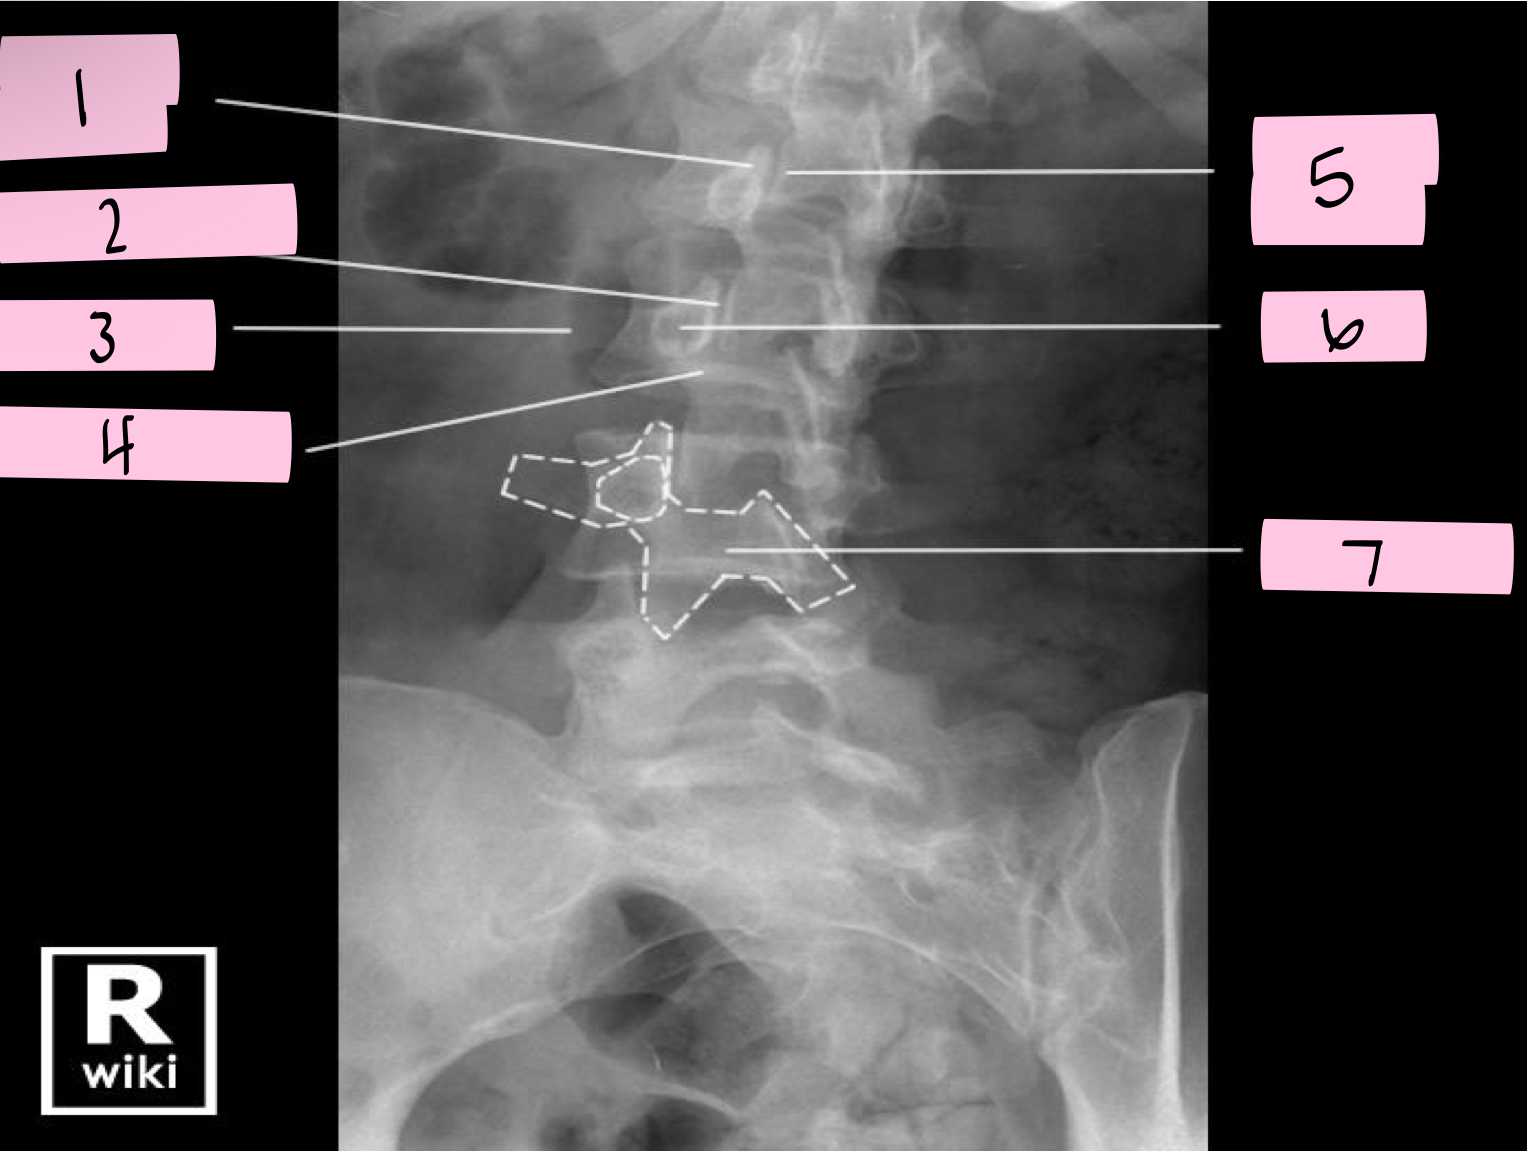

What is 1 pointing to?

Superior articular process

What is 2 pointing to?

Zygapophyseal joint

What is 3 pointing to?

Transverse process

What is 4 pointing to?

Pars interarticularis

What is 5 pointing to?

Inferior articular process

What is 6 pointing to?

Pedicle

What is 7 pointing to?

Scotty dog